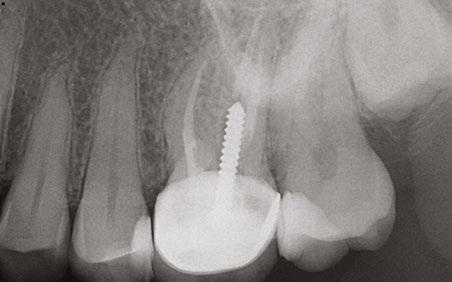

Figure 7: Planned-for access with the scan info on this extremely calcified canine Figures 8 and 9: 8. Deep distal split with PARL. 9. Missed buccal canal; history of previous RCT, post, crown and apico Figure 10: Retreatment consultation. PA from GD Figure 11: Scan images show a previously existing strip perforation

I’m also changing my treatment plans based on the data from my CBCT. Sometimes I look at a root canal treated PA and presume I know what I will do: a retreatment or an apico. Another recent, poignant case: a lower incisor with a previous RCT and a previous apico (Figure 9). Usually, once a tooth has had an apico, there may not be much left to offer and most of the time, the default is another apico, especially as there was very little room for an implant on the lower anteriors. I scanned the tooth and saw that a whole canal had been missed — twice! The RCT and the apico had left the buccal canal completely untouched. I changed my treatment plan based on this information!